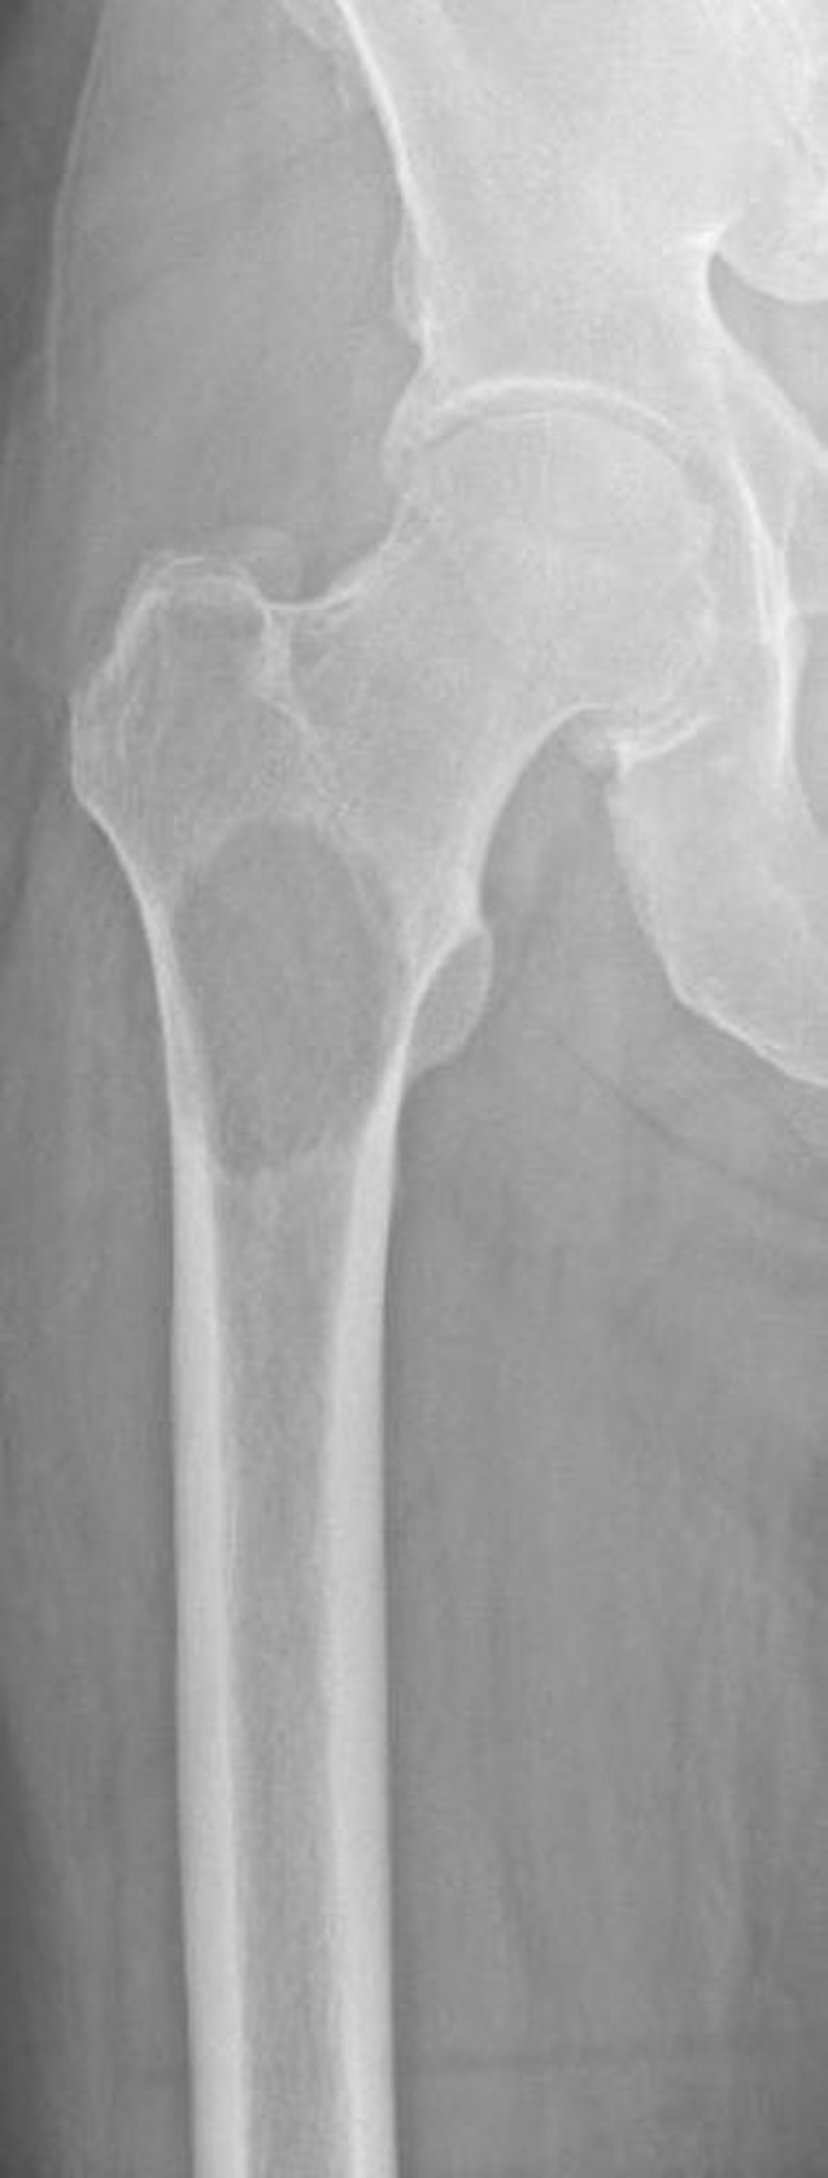

Di căn tiêu xương ở đầu gần xương đùi

Hình ảnh này cho thấy tiêu xương do di căn thứ phát từ ung thư biểu mô tế bào thận ở đầu gần xương đùi. Vị trí và mức độ phá hủy xương làm cho nguy cơ gãy xương cực kỳ cao (nguy cơ gãy xương).

Hình ảnh do bác sĩ Michael J. Joyce và bác sĩ David M. Joyce cung cấp.